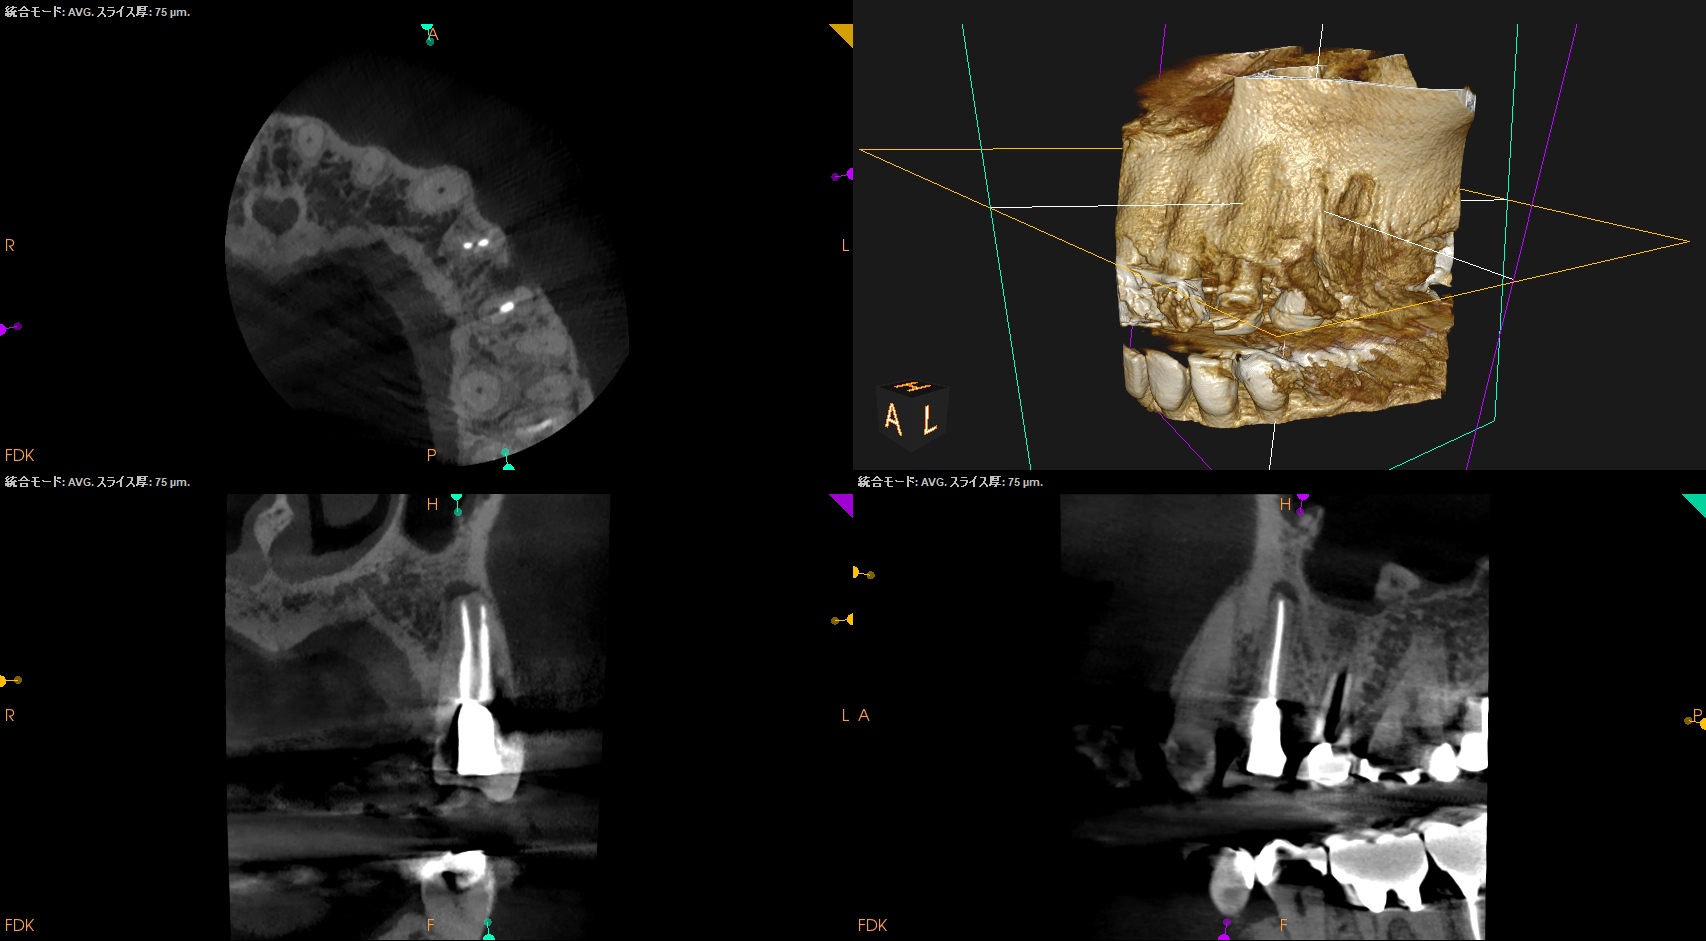

CBCT(2025.8.25)

#12 B

#12 P

#13